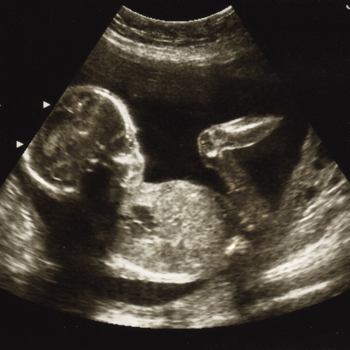

Jangan terlambat. Inilah waktu yang tepat untuk melakukan pemeriksaan USG.... read more